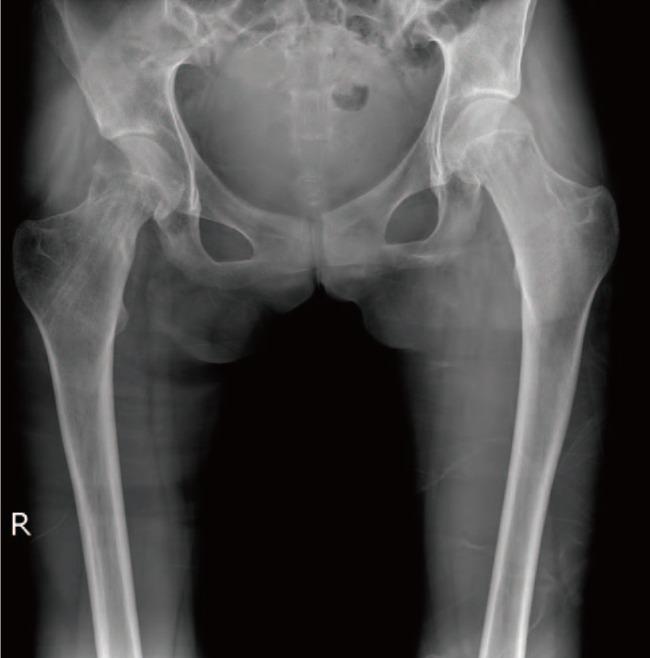

一名年轻马凡综合征患者的股骨颈骨折

Femur Neck Fracture in a Young Marfan Syndrome Patient.

Marfan syndrome is an autosomal dominant and could decrease bone mineral density. So patients with Marfan syndrome could vulnerable to trauma in old ages. We present the first report, to the best of our knowledge, of a rare fracture of the femoral neck with a minor traumatic history in a juvenile Marfan syndrome patient whose physis is still open. Although the patient is young, her bone mineral density was low and the geometry of femur is changed like old ages. The femur neck fracture in children is very rare and only caused by high energy trauma, we concluded that the Marfan syndrome makes the bone weaker in young age and preventative medications to avoid fractures in younger Marfan syndrome patients are necessary in early ages.

摘要

马凡综合征是一种常染色体显性疾病,可导致骨密度降低。因此,马凡综合征患者在老年时易受创伤。据我们所知,我们首次报告了一名骨骺仍未闭合的青少年马凡综合征患者,其股骨颈发生罕见骨折,且外伤史轻微。尽管患者年轻,但她的骨密度较低,股骨形态已如老年人般改变。儿童股骨颈骨折非常罕见,通常仅由高能量创伤引起,我们得出结论,马凡综合征会使年轻人的骨骼更脆弱,因此有必要在早期对年轻的马凡综合征患者采取预防措施以避免骨折。